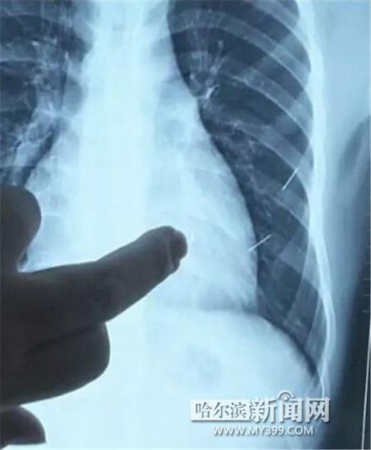

昨日上午,记者在哈医大二院第八住院部心外三病房找到了躺在病床上痛苦不堪的董立仁,家属正在他身旁不断安慰着他。见记者前来,董立仁母亲李百燕拿出一张X光片,上面可以清晰地看到胸腔内一共有4根针状物,其中一根在心脏部位,两根在胸腔壁上,还有一根在腹腔壁上。

心外三病房董立仁的主治医生告诉记者,董立仁送到医院时病情很危险,随时可能危及生命。“通过检查发现,他心脏内有一个金属异物,正好在心脏上。心脏每次跳动都与其产生摩擦,导致出血,心包积液怀疑是血液。如果大量出血会凝结成血块,血块包裹住心脏就会影响心脏跳动,随时都有停跳的危险。心脏上的异物是致命伤,其余胸腔壁和腹腔壁的异物伤害不大。”

昨天16时30分左右取针手术开始。因钢针随时会危及患者生命,此次手术定义为大型手术。开胸后,医生打开董立仁心包,发现一枚钢针已深深扎入心脏,仅露出1厘米长度在外。拔出钢针后,医生发现,这枚针长达5厘米。受钢针影响,心包出现大量积液,近800毫升。

随后,在下胸壁位置,第二枚钢针顺利取出。在寻找另两枚钢针过程中,普外、胸外多名医生也参与手术,为主刀医生提供更为稳妥的处理建议。根据X光片显示位置,医生未在患者体内找到剩余两枚钢针。医生怀疑,其中一枚钢针可能深藏在肋骨骨膜位置,无法寻找,最后决定结束手术,做进一步观察,研究下一次手术方案。